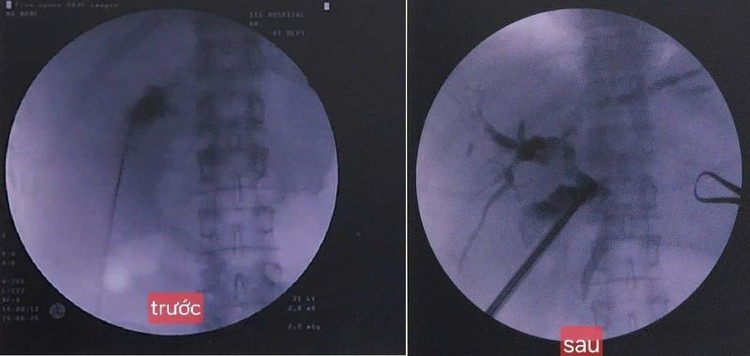

soi.jpg

Hình ảnh trước và sau can thiệp - Ảnh BVCC